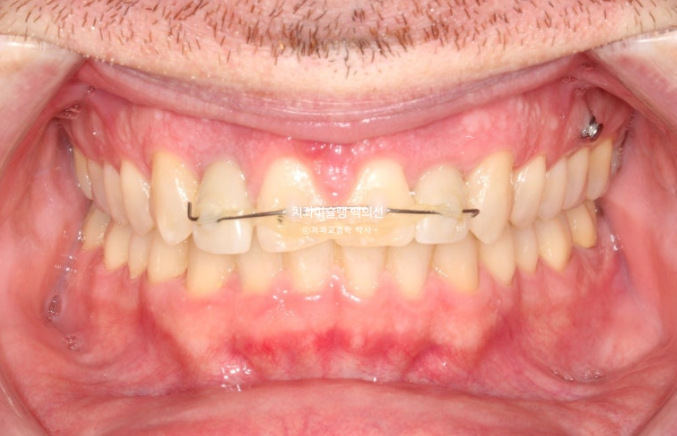

중심선은 잘 맞고 과개교합은 깔끔하게 개선이 되었습니다.

어금니 교합은 물샐틈 없이 좋고 1급 교합관계를 보입니다.

이제 전 후 비교 보겠습니다.

치료기간은 1년 9개월, 재발된 앞니 치축을 바로 잡는데는 4개월이 걸렸습니다.